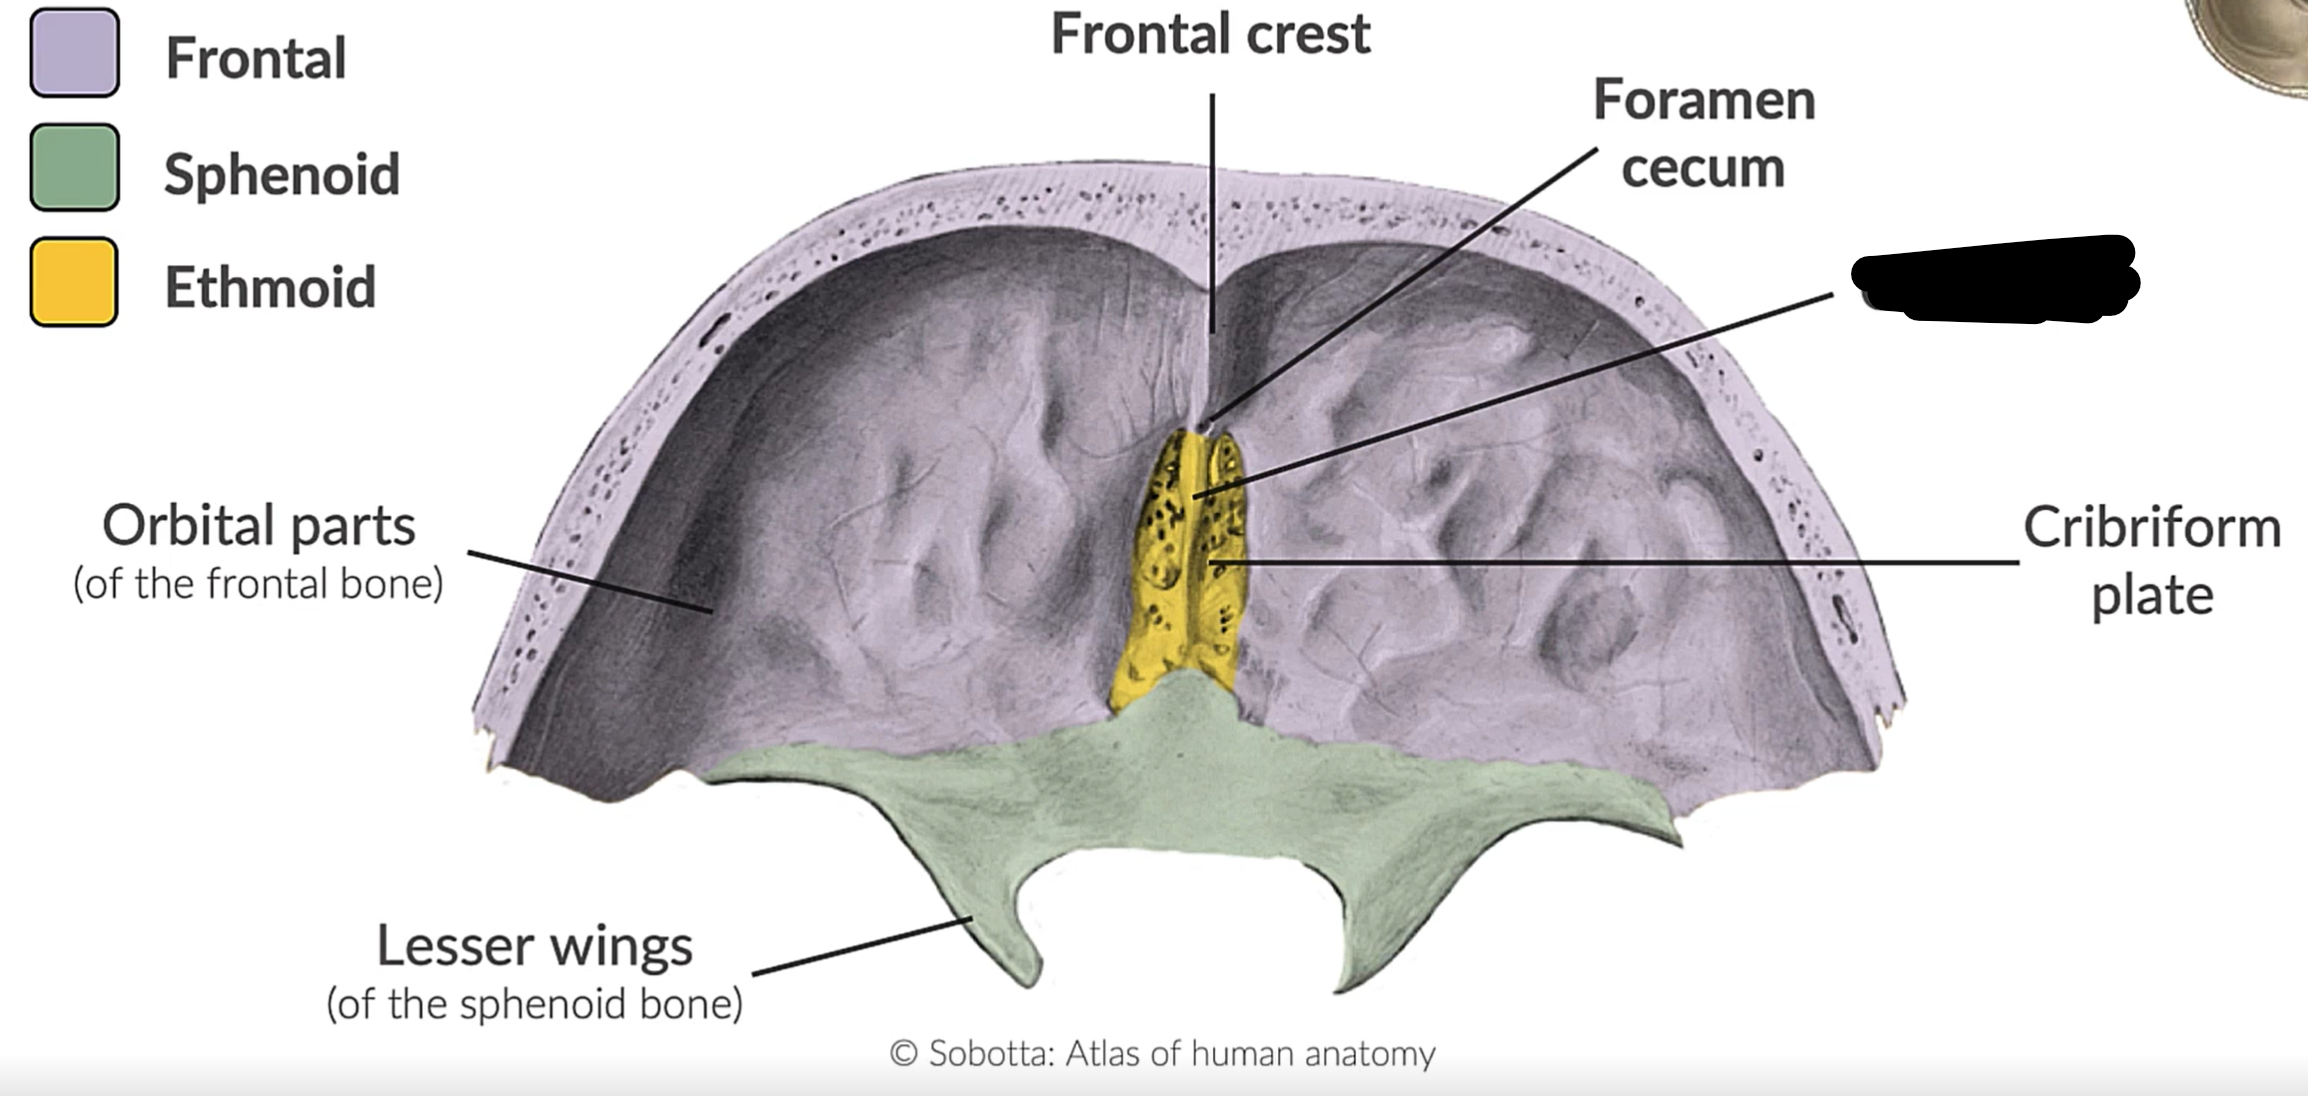

What bones form the anterior cranial fossa?

Frontal, ethmoid and sphenoid

What is this?

Anterior cranial fossa

What is this?

Cribriform plate

NN

Crista galli

Foramen caecum